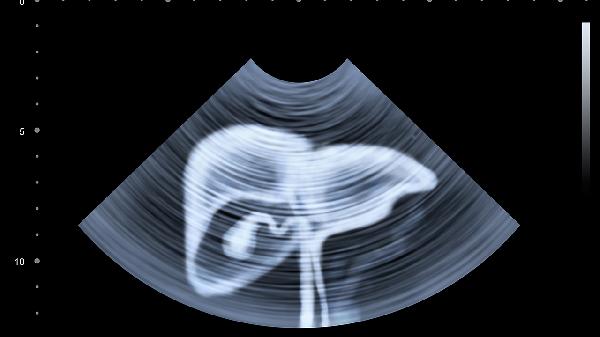

肠梗阻患者除腹胀腹痛外,常伴有停止排便排气、呕吐等症状。机械性梗阻可能与肠粘连、肿瘤等因素有关,需通过影像学检查确诊。轻度病例可通过禁食、胃肠减压缓解,严重者需手术解除梗阻。